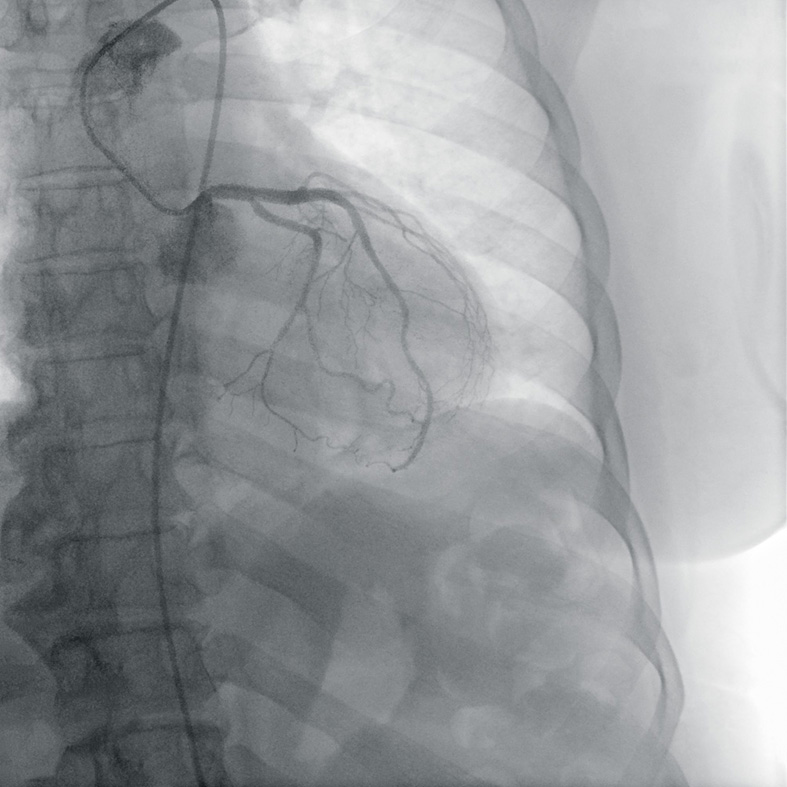

新光医院心脏内科医生陈冠任指出,低密度胆固醇(LDL),也就是俗称的坏胆固醇,与心脏病、脑中风等重大心血管疾病有高度关联。一旦数值长期偏高,血管内壁容易堆积脂肪斑块,增加突发性风险。

他强调,许多人误以为只有肥胖、不爱运动的人才会胆固醇超标,但临床上并非如此。曾有一名39岁的上班族,体格结实、经常健身,却在运动时突然胸口不适,随后倒地失去心跳,经紧急送医才发现是急性心肌梗塞,血管严重阻塞。追溯病史发现,他早在健康检查时就已被告知坏胆固醇过高,却始终未加理会。另一个案例是一名身材瘦小的20岁女大学生,坏胆固醇数值高达200 mg/dL,远超建议的130 mg/dL以下标准,最终需接受药物治疗。